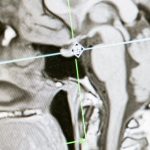

La thérapie laser a prouvé son efficacité dans le traitement des douleurs cervicales et des blessures sportives. Des études ont démontré que l’application du laser peut réduire significativement la douleur liée aux douleurs cervicales et aux complications liées à des blessures répétitives.

La thérapie au laser est une méthode de traitement moderne qui fait appel à la lumière laser pour favoriser la guérison et soulager la douleur. Utilisée principalement pour traiter les douleurs chronique et les blessures sportives, cette approche non invasive s’inscrit dans une philosophie de soins centrée sur l’efficacité et la science. Les lasers non ablatifs envoient des longueurs d’onde précises pour stimuler la régénération des tissus tout en réduisant les signes d’inflammation comme l’œdème et la douleur.

Avec les avancées technologiques, les équipements de thérapie au laser deviennent de plus en plus sophistiqués, offrant des traitements personnalisés et adaptés aux besoins spécifiques de chaque patient. C’est particulièrement pertinent dans le cadre de l’arthrose ou des hernies discales, où les options de traitement traditionnelles peuvent ne pas suffire. La thérapie au laser émerge ainsi comme une alternative non chirurgicale, acceptée et recommandée par de nombreux professionnels de la santé.